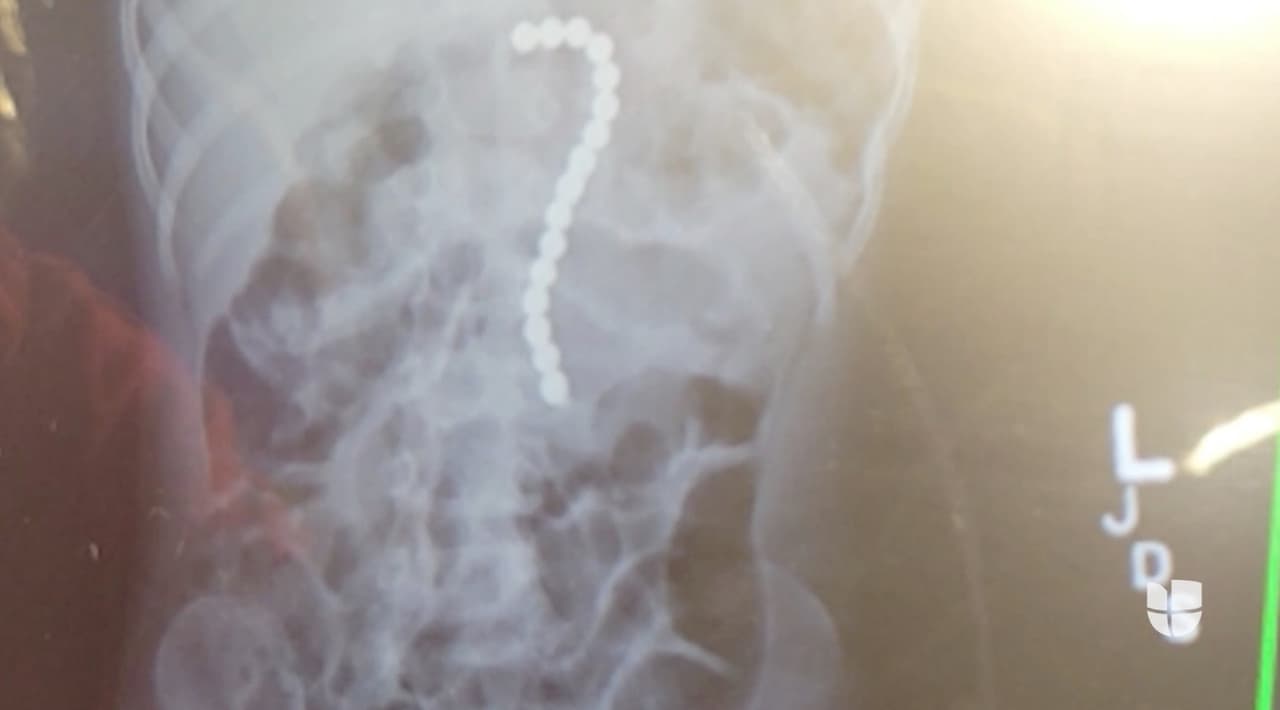

El niño de 2 años, quien vive en la ciudad de Orlando, se tragó las 16 bolas magnéticas después de que uno de sus hermanos las trajo del colegio. Tuvieron que hacerle una cirugía para sacárselas.